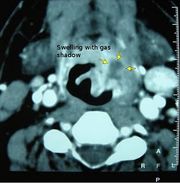

| 01:43, 23 October 2018 | Ctlud.jpg (file) |  |

41 KB | Drtbalu | |